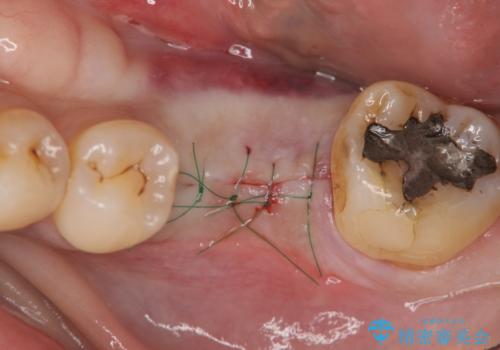

- 外科手術のため、術後に痛みや腫れ、違和感を伴います

- メンテナンスを怠ったり喫煙により、お口の中に大きな悪影響を及ぼすインプラント周囲炎等にかかる可能性があります

元あった歯のようにしっかりと咬合機能が回復することができました。